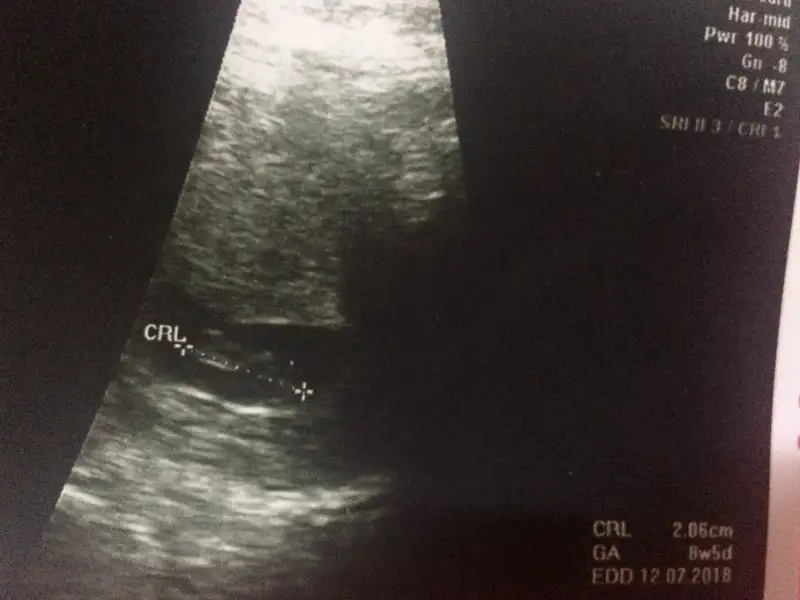

Bu arada Allahım bağışlasın evlatlarını canım. Bide benim ikisinde de ayrı ultrason resmi ekledim biri fasulye :) çarşamba nasıl olacak bakalım çok heycanlıyım

Eklentiler

• 0D36B26E-F23E-47E7-B70F-327633403338.webp

0D36B26E-F23E-47E7-B70F-327633403338.webp

18 KB · Görüntüleme: 88

• F8604ACB-9F5D-455D-AFAA-175391BB23B8.webp

F8604ACB-9F5D-455D-AFAA-175391BB23B8.webp

19,3 KB · Görüntüleme: 84